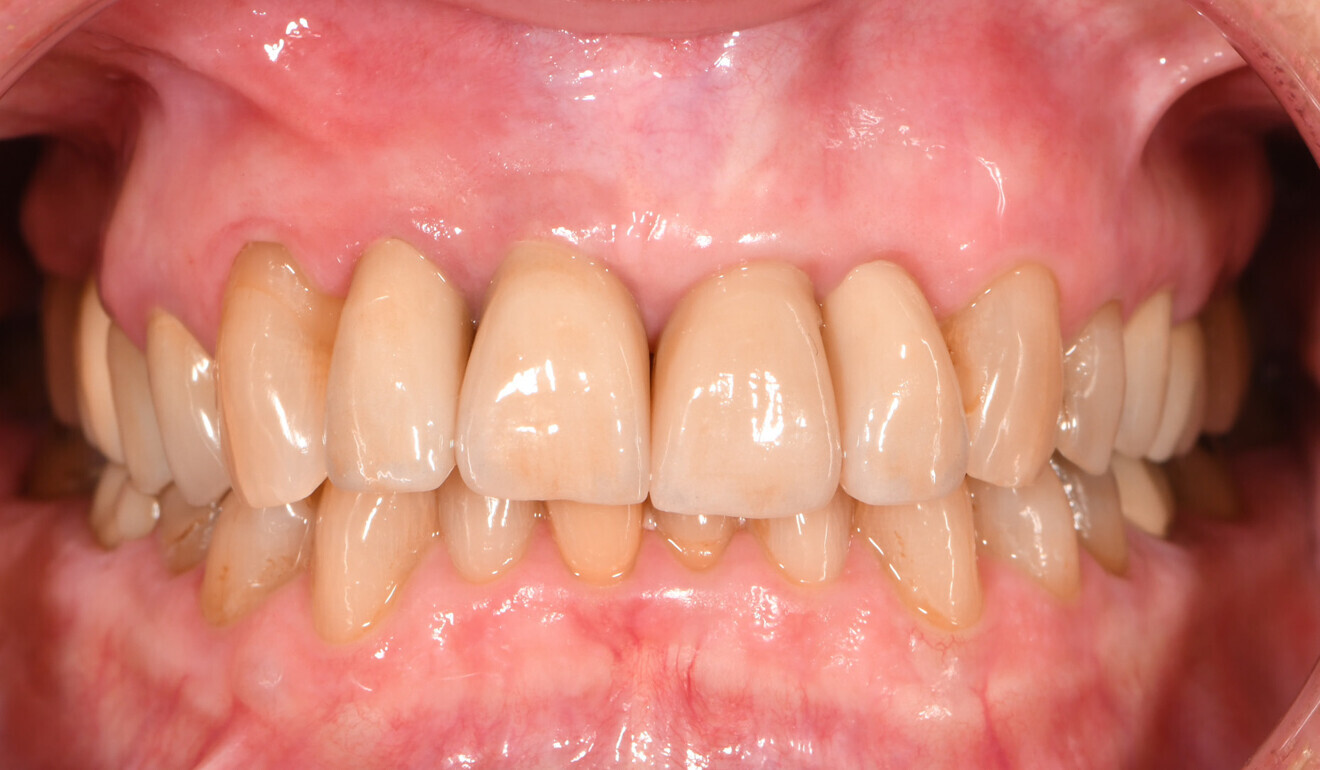

Fig. 14: Immediate treatment outcome, frontal view.

Based on the data set of the temporary restorations, four separate crowns—one for the implant and three for the teeth—were designed in full contour. Without any anatomical reduction, the restorations were milled from KATANA Zirconia YML. Based on the evaluation of the temporary restorations, the shade selected this time was Shade A3.5. CERABIEN ZR FC Paste Stain (Kuraray Noritake Dental) was used for external staining and glazing of the surface. The laboratory also cemented the implant-based crown to the gold-shaded titanium abutment (Elos Medtech) with PANAVIA V5 (Kuraray Noritake Dental) in the shade Opaque for an improved masking effect (Fig. 11). In the office, the abutment–crown was screwed on to the implant and the screw access hole closed with composite, and the three tooth-based crowns were then placed using PANAVIA SA Cement Universal (Figs. 12–15).

Multilayered zirconia is a suitable material for many clinical situations. Owing to the availability of highly translucent multilayered blanks, it is now possible to produce aesthetic outcomes even when using the material monolithically, and this is true not only in the posterior region but in the aesthetic zone in some cases too. The present case demonstrated that very good results and patient satisfaction can be obtained. Moreover, as a result of the material’s outstanding mechanical properties, these outcomes may be expected to last for a long time.